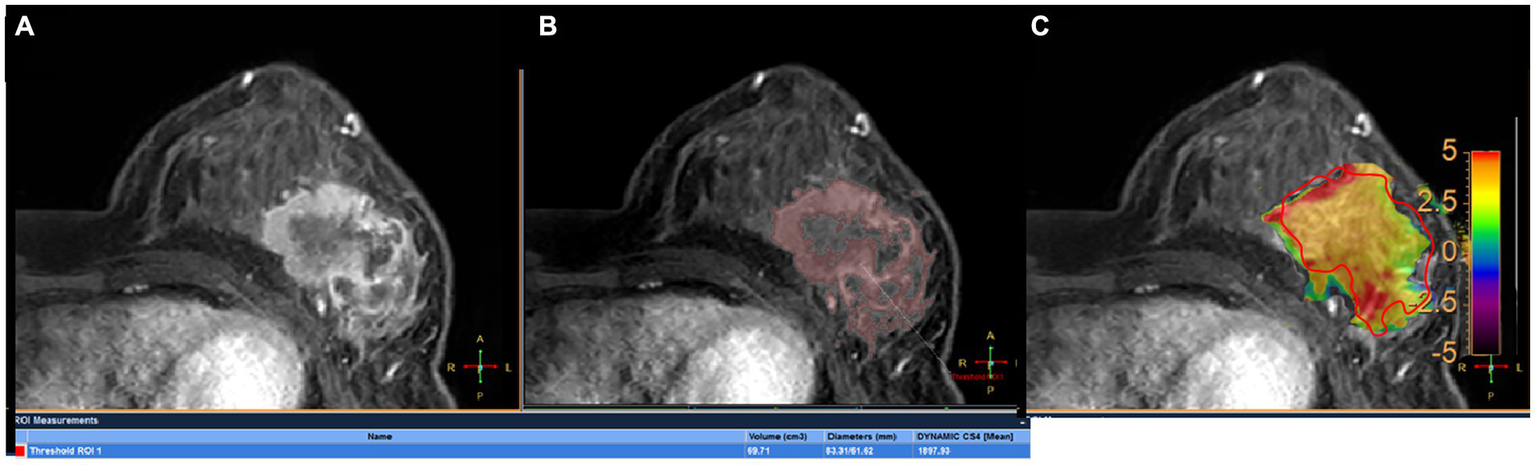

Figure 2

A 45-year-old woman with grade III invasive ductal breast cancer: a 43-year-old woman with grade III invasive breast cancer: (A) image of DCE, (B) the volume of interest was also determined on the contrast enhanced image using a threshold method, and the Dmax and V measured for tumor were 83.31 mm and 69.71 mm3, respectively. (C) the tumor region of interest was determined on the contrast enhanced image and copied to the APTw image for APTw value measurement (APTw = 3.51 ± 1.23).

All images were analyzed with the IntelliSpace Portal (ISP, Philips Healthcare, Cleveland, OH, United States) workstation. The magnetization transfer ratio with asymmetric analysis at +3.5 ppm (MTRasym [+3.5 ppm]) for each image voxel was carried out to generate APTw maps from raw images in real time on the console with Z-spectrum fitting and B0 correction (14), where values in the maps refer to differences between the signal intensities at ±3.5 ppm of water proton resonance, as percentages of the signal intensities when the saturation pulse applied is far off resonance. Image analysis was carried out by two breast radiologists (readers 1 and 2 with 13 and 6 years of experience in imaging diagnosis, respectively, blinded to final pathological results and other clinical data). In each patient, APTw maps were firstly fused onto DCE images at approximately the same slice position (22), and a 2D region of interest (ROI) was delineated on the slice transecting the largest area of the lesion. The ROIs included the most enhanced lesion regions on DCE images while avoiding cystic or necrotic lesions (Figure 2A). The maximum diameter (Dmax) and 3D volume (V) of each tumor were measured on DCE images. The threshold extraction method of the MR Segmentation software on the workstation (Intellispace Portal v7.0, Philips Healthcare) was used to extract the tumor as a whole, and the software automatically yielded Dmax and V (Figures 2B,C). Apparent diffusion coefficient (ADC) values were measured on DWI images. APTw, V, Dmax and ADC values at the time points T0 and T1 were annotated as APTw0, APTw1, V0, V1, Dmax0, Dmax1, ADC0 and ADC1, and changes in APTw, V, Dmax and ADC values at T1 relative to T0 were termed ΔAPTw, ΔV, ΔDmax and ΔADC, respectively.